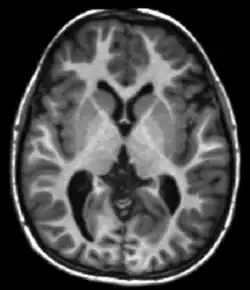

Each tissue returns to its equilibrium state after excitation by the independent relaxation processes of T1 (spin-lattice; that is, magnetization in the same direction as the static magnetic field) and T2 (spin-spin; transverse to the static magnetic field). To create a T1-weighted image, magnetization is allowed to recover before measuring the MR signal by changing the repetition time (TR). This image weighting is useful for assessing the cerebral cortex, identifying fatty tissue, characterizing focal liver lesions, and in general, obtaining morphological information, as well as for post-contrast imaging. To create a T2-weighted image, magnetization is allowed to decay before measuring the MR signal by changing the echo time (TE). This image weighting is useful for detecting edema and inflammation, revealing white matter lesions, and assessing zonal anatomy in the prostate and uterus.

The information from MRI scans comes in the form of image contrasts based on differences in the rate of relaxation of nuclear spins following their perturbation by an oscillating magnetic field (in the form of radiofrequency pulses through the sample).[19] The relaxation rates are a measure of the time it takes for a signal to decay back to an equilibrium state from either the longitudinal or transverse plane.